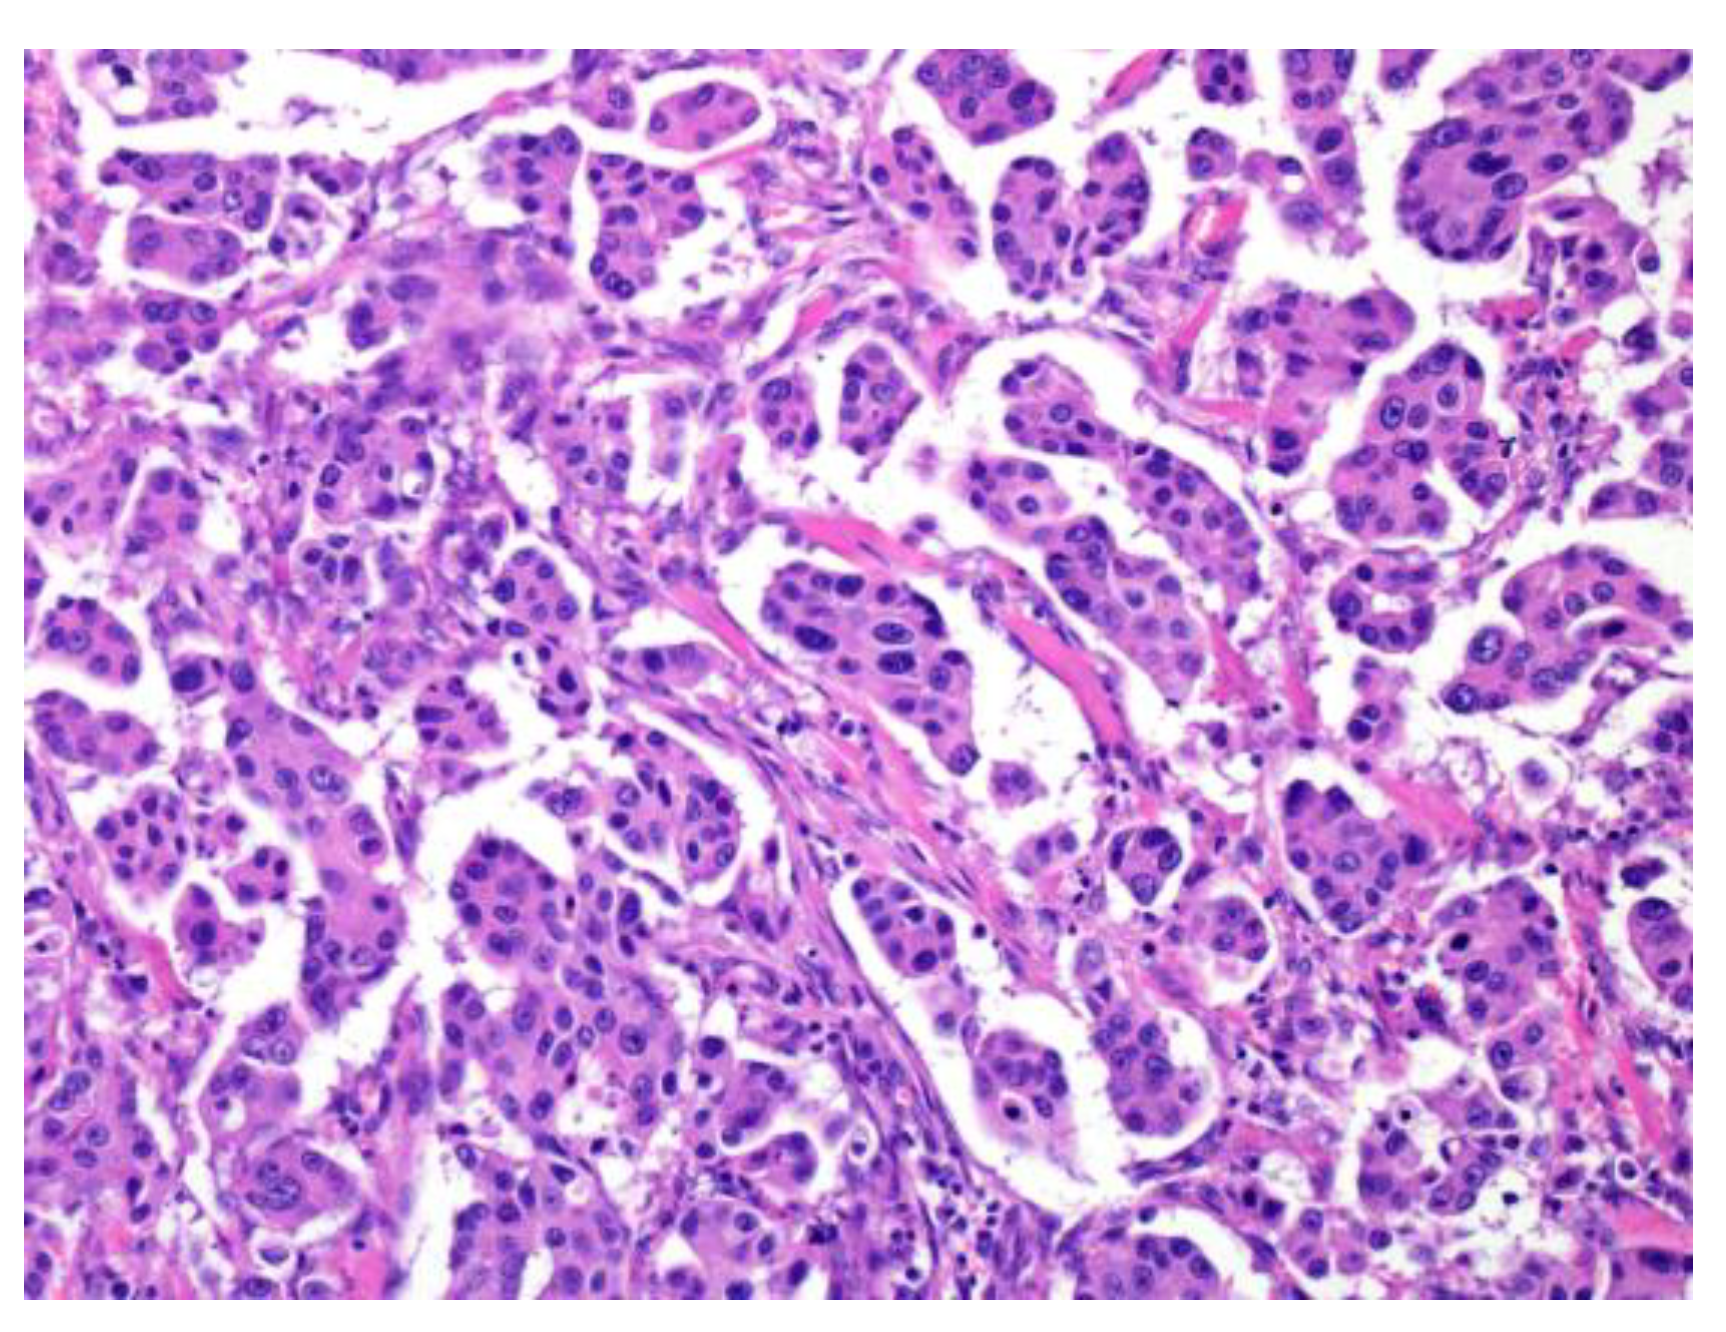

Figure 4.

The morphological features of low/intermediate mucoepidermoid carcinoma (MEC). The tumor forms cystic (a; low grade) and solid growth patterns (b; intermediate). In both cases, tumor cell atypia is mild, but the intermediate category shows slightly different nuclear sizes with mitosis.

MEC is characterized by mucous, as we intermediate and epidermoid/squamoid tumor cells. However, in some tumors, intermediate cells are predominant. MEC forms cystic and solid growth patterns that are usually associated with MAML2 rearrangement [2,39] (Bishop, J.A. et al. pp. 265–290); therefore, some reports describe the histological features for grading (Table 3, Figure 4) [2,39,40,41,42,43], which include structural atypia (cystic/solid component, border invasion pattern, lymphovascular/perineural invasion, and necrosis) and cytological atypia (nuclear anaplasia/pleomorphism and mitoses) [2,36,37,38,39,40,41,42,43]. According to these gradings, MEC should be graded as low, intermediate, or high. The higher the grade, the greater the possibility of metastasis or recurrence [2,39] (Bishop, J.A. et al. pp. 265–290).